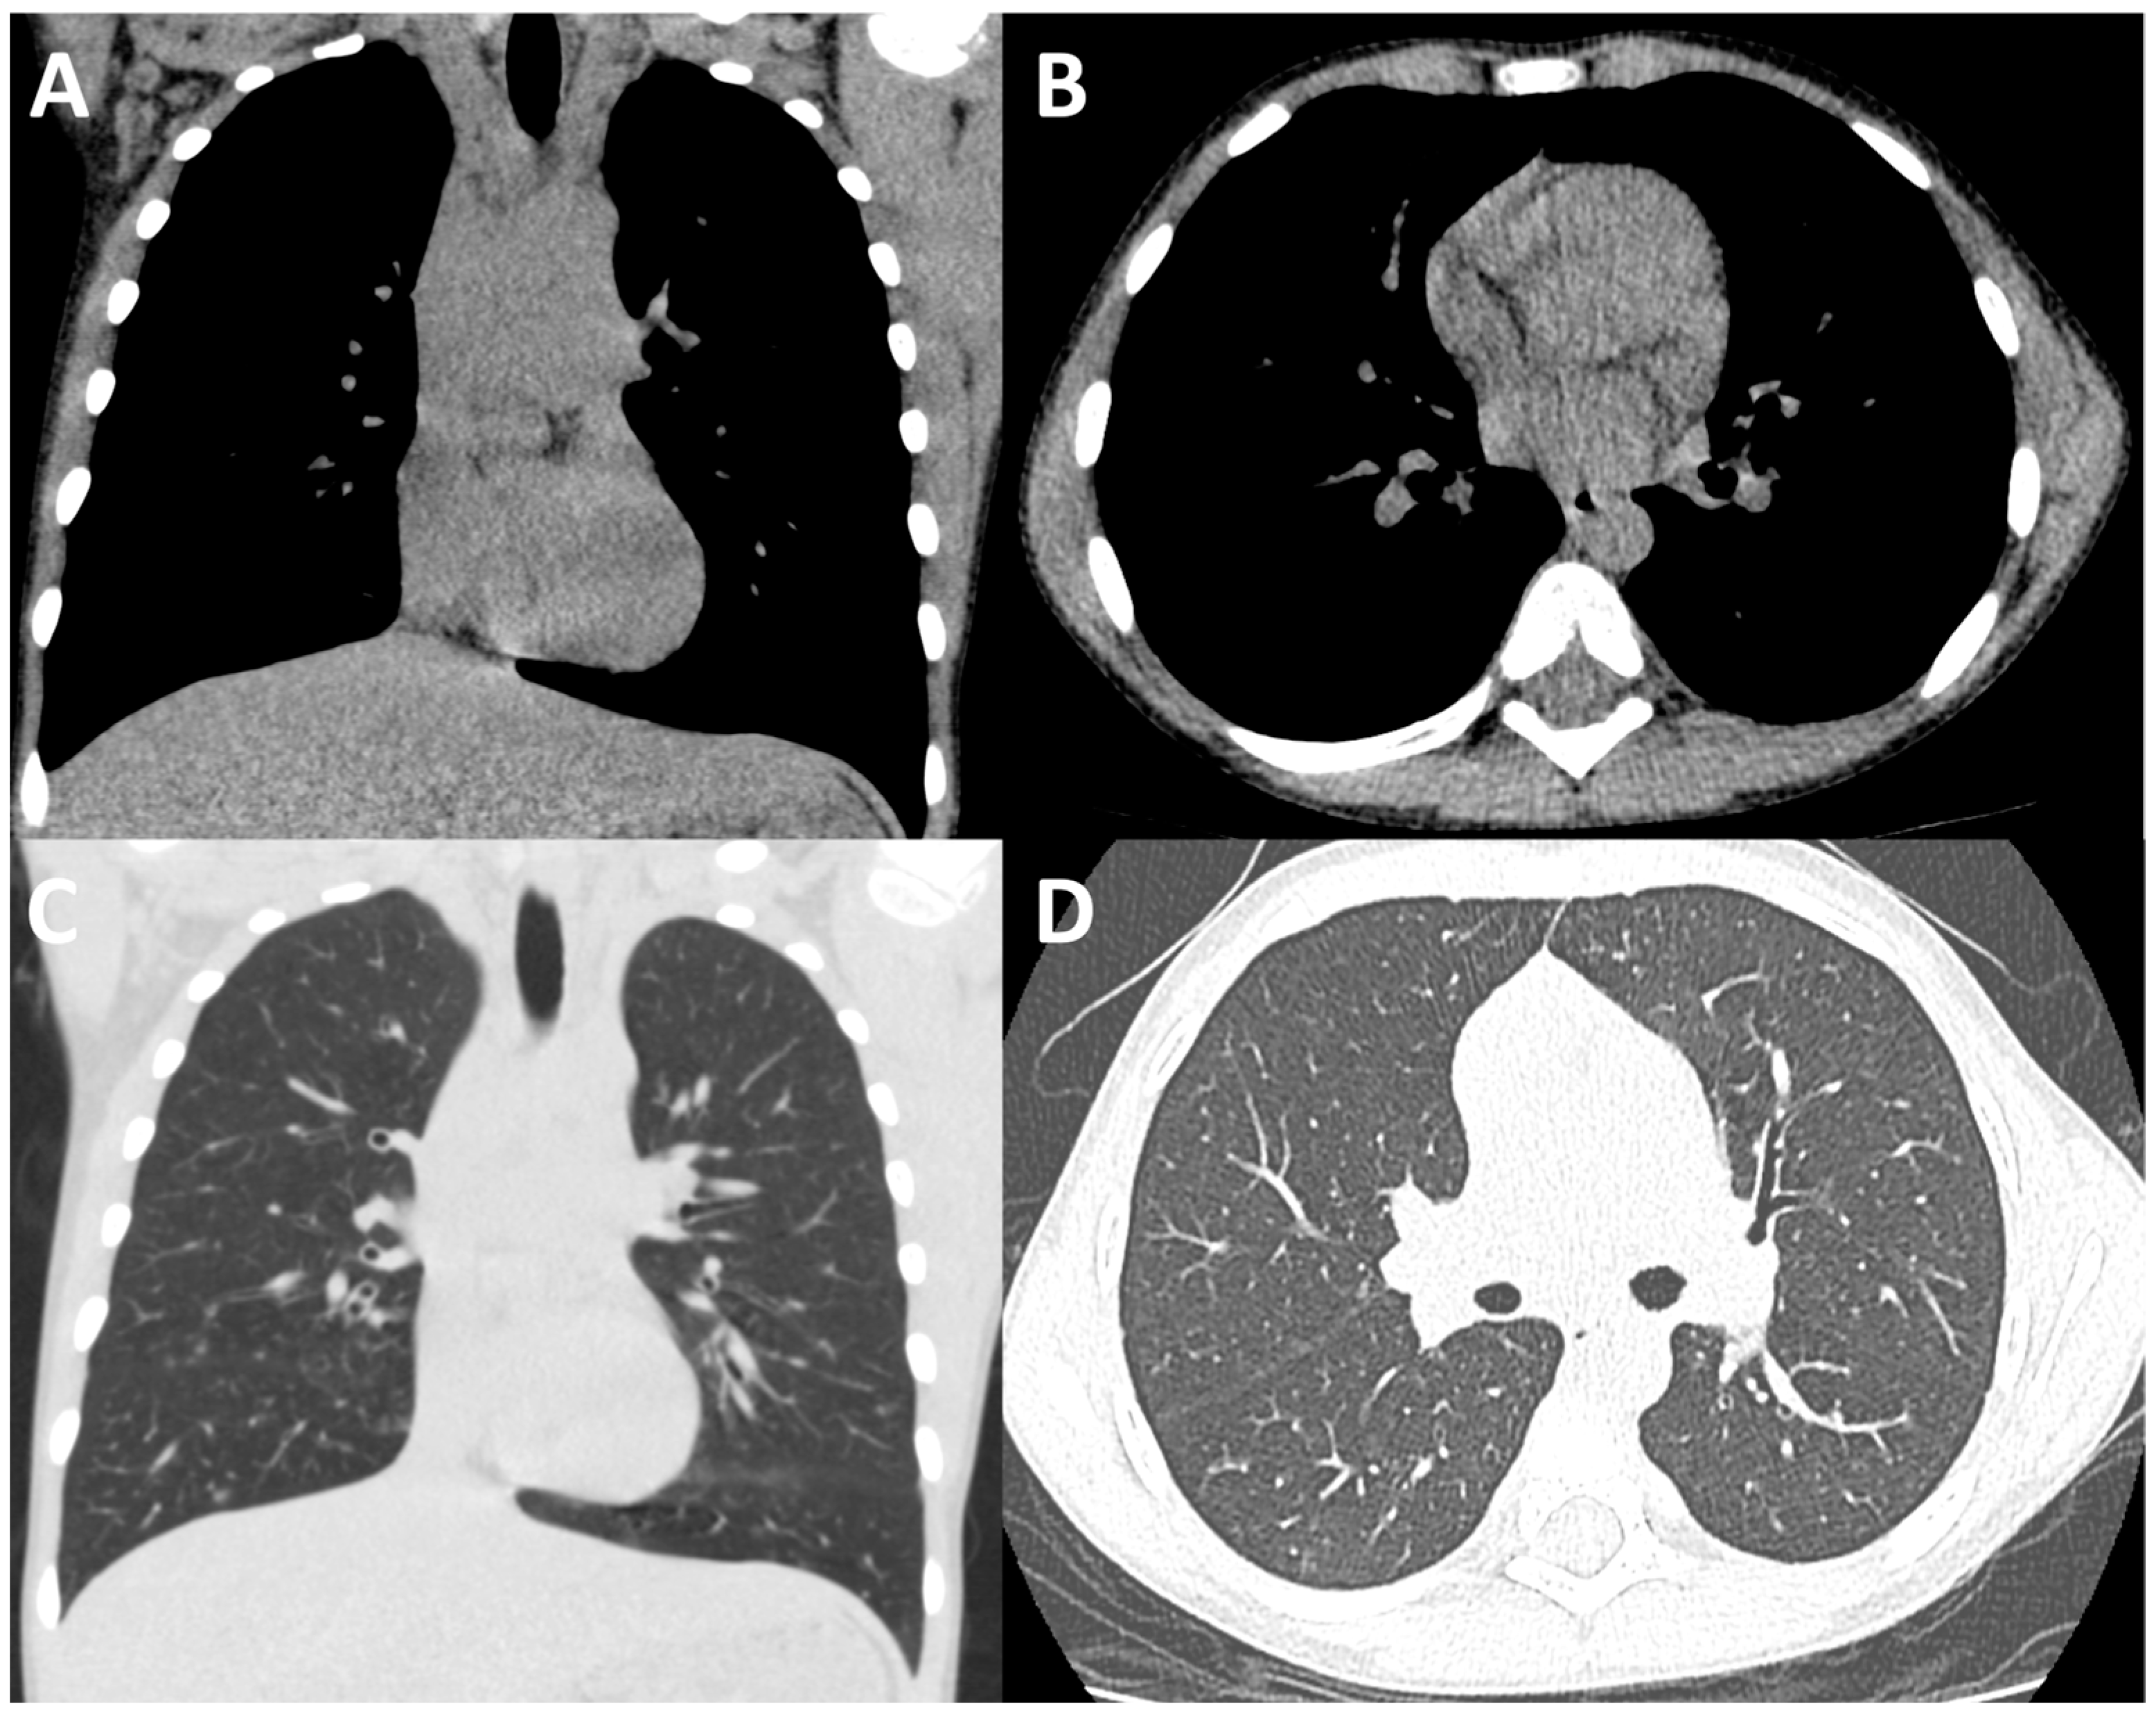

- Moloney, F.; Kavanagh, R.G.; Ronan, N.J.; Grey, T.M.; Joyce, S.; Ryan, D.J.; Moore, N.; O’Connor, O.J.; Plant, B.J.; Maher, M.M. Ultra-low-dose thoracic CT with model-based iterative reconstruction (MBIR) in cystic fibrosis patients undergoing treatment with cystic fibrosis transmembrane conductance regulators (CFTR). Clin. Radiol. 2021, 76, 393.e9–393.e17. [Google Scholar] [CrossRef] [PubMed]